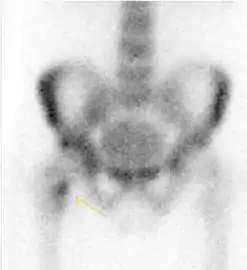

Figure 10:

Stress femoral neck fracture in a young athlete barely visible in X-ray film as a sclerotic line (arrow)[1]

In this case, Tc 99 scintigraphy shows a band of uptake[1]

Furthermore, T1 (left) and DP fat saturated (right) weighted MR images showed the fracture line and a pattern of edema.[1]